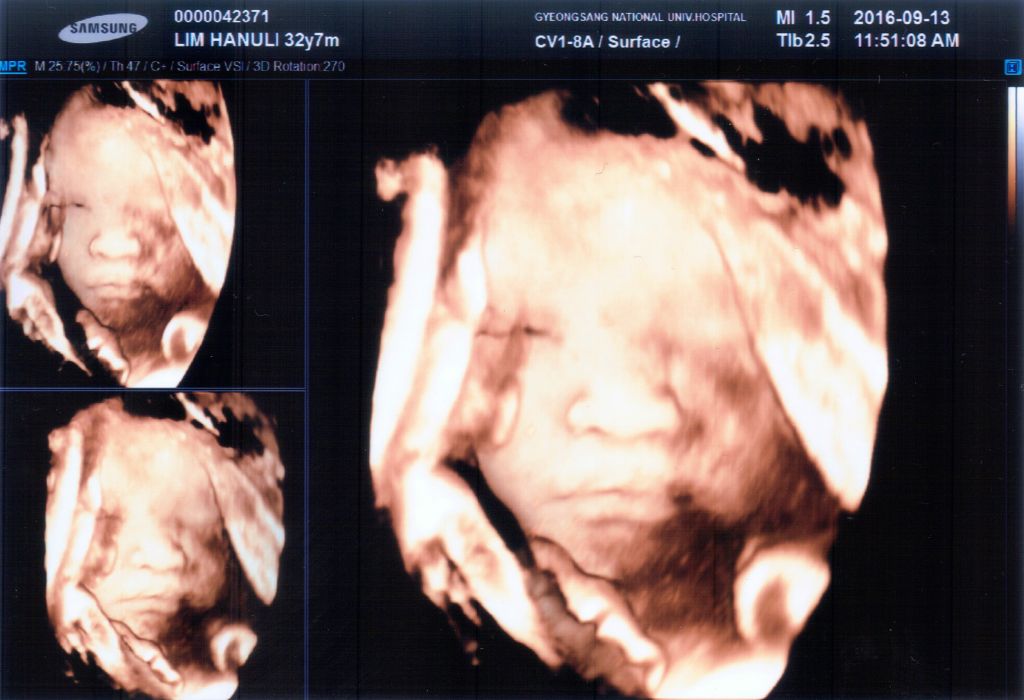

우리 가정에 기다리고 기다리던 새가족이 왔습니다^^ 2016년 10월 26일. 예정일을 지나서도 엄마 뱃속이 좋다며 나오지 않으려는 별이. 의사 선생님과 상담하여 유도분만을 시도하기로 한 날이되어 아침부터 병원으로 향했습니다. 촉진제를 맞고 얼마 되지 않아 진통이 시작되었습니다. 진통하는 동안 수시로 태동검사를 하더라구요. 진통과 분만에 도움이 된다하여 틈틈이 짐볼을 가지고 운동했어요. 부모와 할머니 할아버지들의Read More →